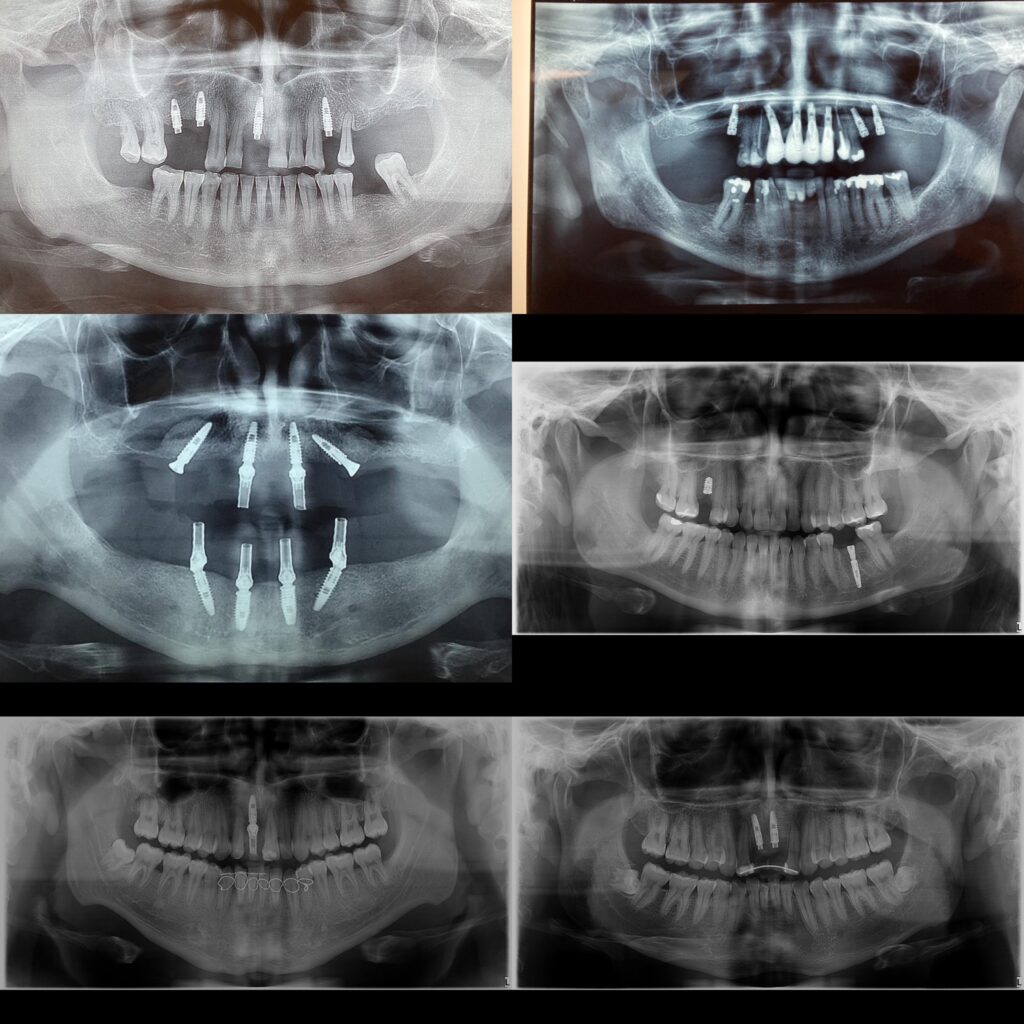

- Evaluación inicial: Se realiza una evaluación clínica y radiográfica para determinar si el paciente es adecuado para el implante.

- Colocación del implante: Se realiza un procedimiento quirúrgico para insertar el implante en el hueso de la mandíbula.

- Fase de osteointegración: El implante debe integrarse al hueso, lo que puede tardar entre 3 a 6 meses.

- Colocación del pilar y la corona: Una vez que el implante está integrado al hueso, se coloca el pilar y la corona final.